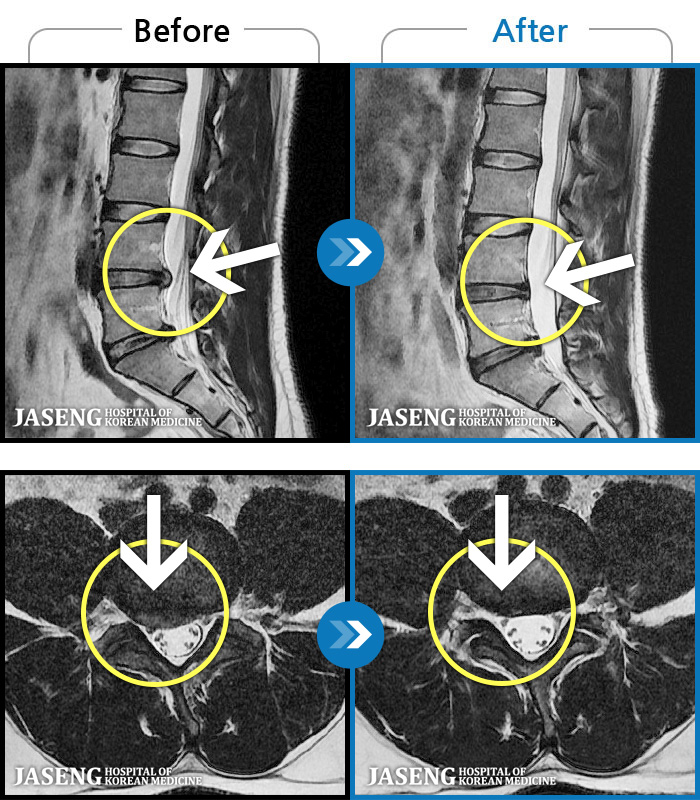

[] 03.04.01~09.11.01

ȯںп Ǹ ǿ ԿǾ, ο ġ ۿ Ƿ ġḦ Ͻñ ٶϴ.